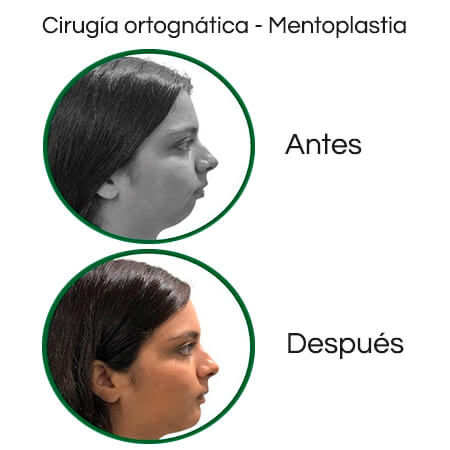

Didenti offers a wide range of services, including orthodontics, cosmetic dentistry, maxillofacial surgery, dental implants, oral rehabilitation, periodontics and endodontics. Doctors Fragozo and Rodríguez offer personalized care backed by the most advanced technology.

Before and After Gallery